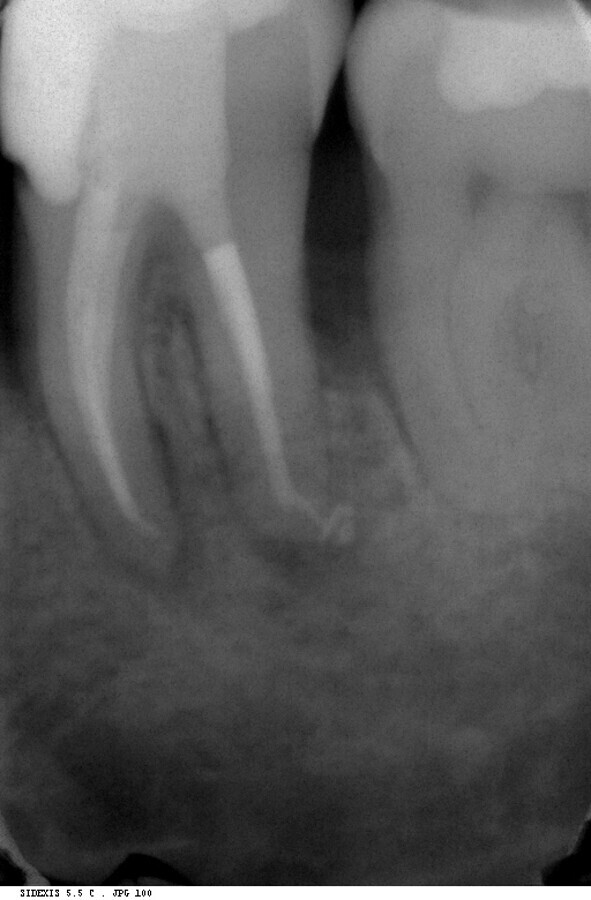

A revision treatment by Dr Silviu Bondari from Beuzeville in France also demonstrates that retreatment can be performed quickly and easily with the new endodontic motor. In a 30-year-old patient, removal of the insufficient gutta- percha filling also proved necessary owing to periapical periodontitis in tooth #36 (Fig. 4). At a speed of 1,000 rpm with continuous rotation, a delicate MicroMega Remover file was inserted to over two-thirds of the distal root canal length. The remainder of the root was then treated with a HyFlex EDM OneFile in the contra-angle handpiece at 500 rpm. HyFlex EDM files of size 20/.05 were used in the mesial root canals. The speed was also set at 500 rpm. The HyFlex EDM OneFile was then used in the mesial canals for final shaping of the root canal. A 40/.04 EDM file was used in the distal root canal. The result on the radiograph promised a more durable obturation than the initial treatment five years earlier (Figs. 5 & 6).